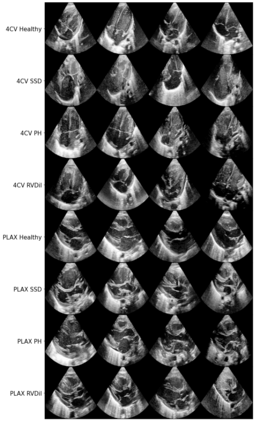

We propose a novel anomaly detection method for echocardiogram videos. The introduced method takes advantage of the periodic nature of the heart cycle to learn different variants of a variational latent trajectory model (TVAE). The models are trained on the healthy samples of an in-house dataset of infant echocardiogram videos consisting of multiple chamber views to learn a normative prior of the healthy population. During inference, maximum a posteriori (MAP) based anomaly detection is performed to detect out-of-distribution samples in our dataset. The proposed method reliably identifies severe congenital heart defects, such as Ebstein's Anomaly or Shonecomplex. Moreover, it achieves superior performance over MAP-based anomaly detection with standard variational autoencoders on the task of detecting pulmonary hypertension and right ventricular dilation. Finally, we demonstrate that the proposed method provides interpretable explanations of its output through heatmaps which highlight the regions corresponding to anomalous heart structures.